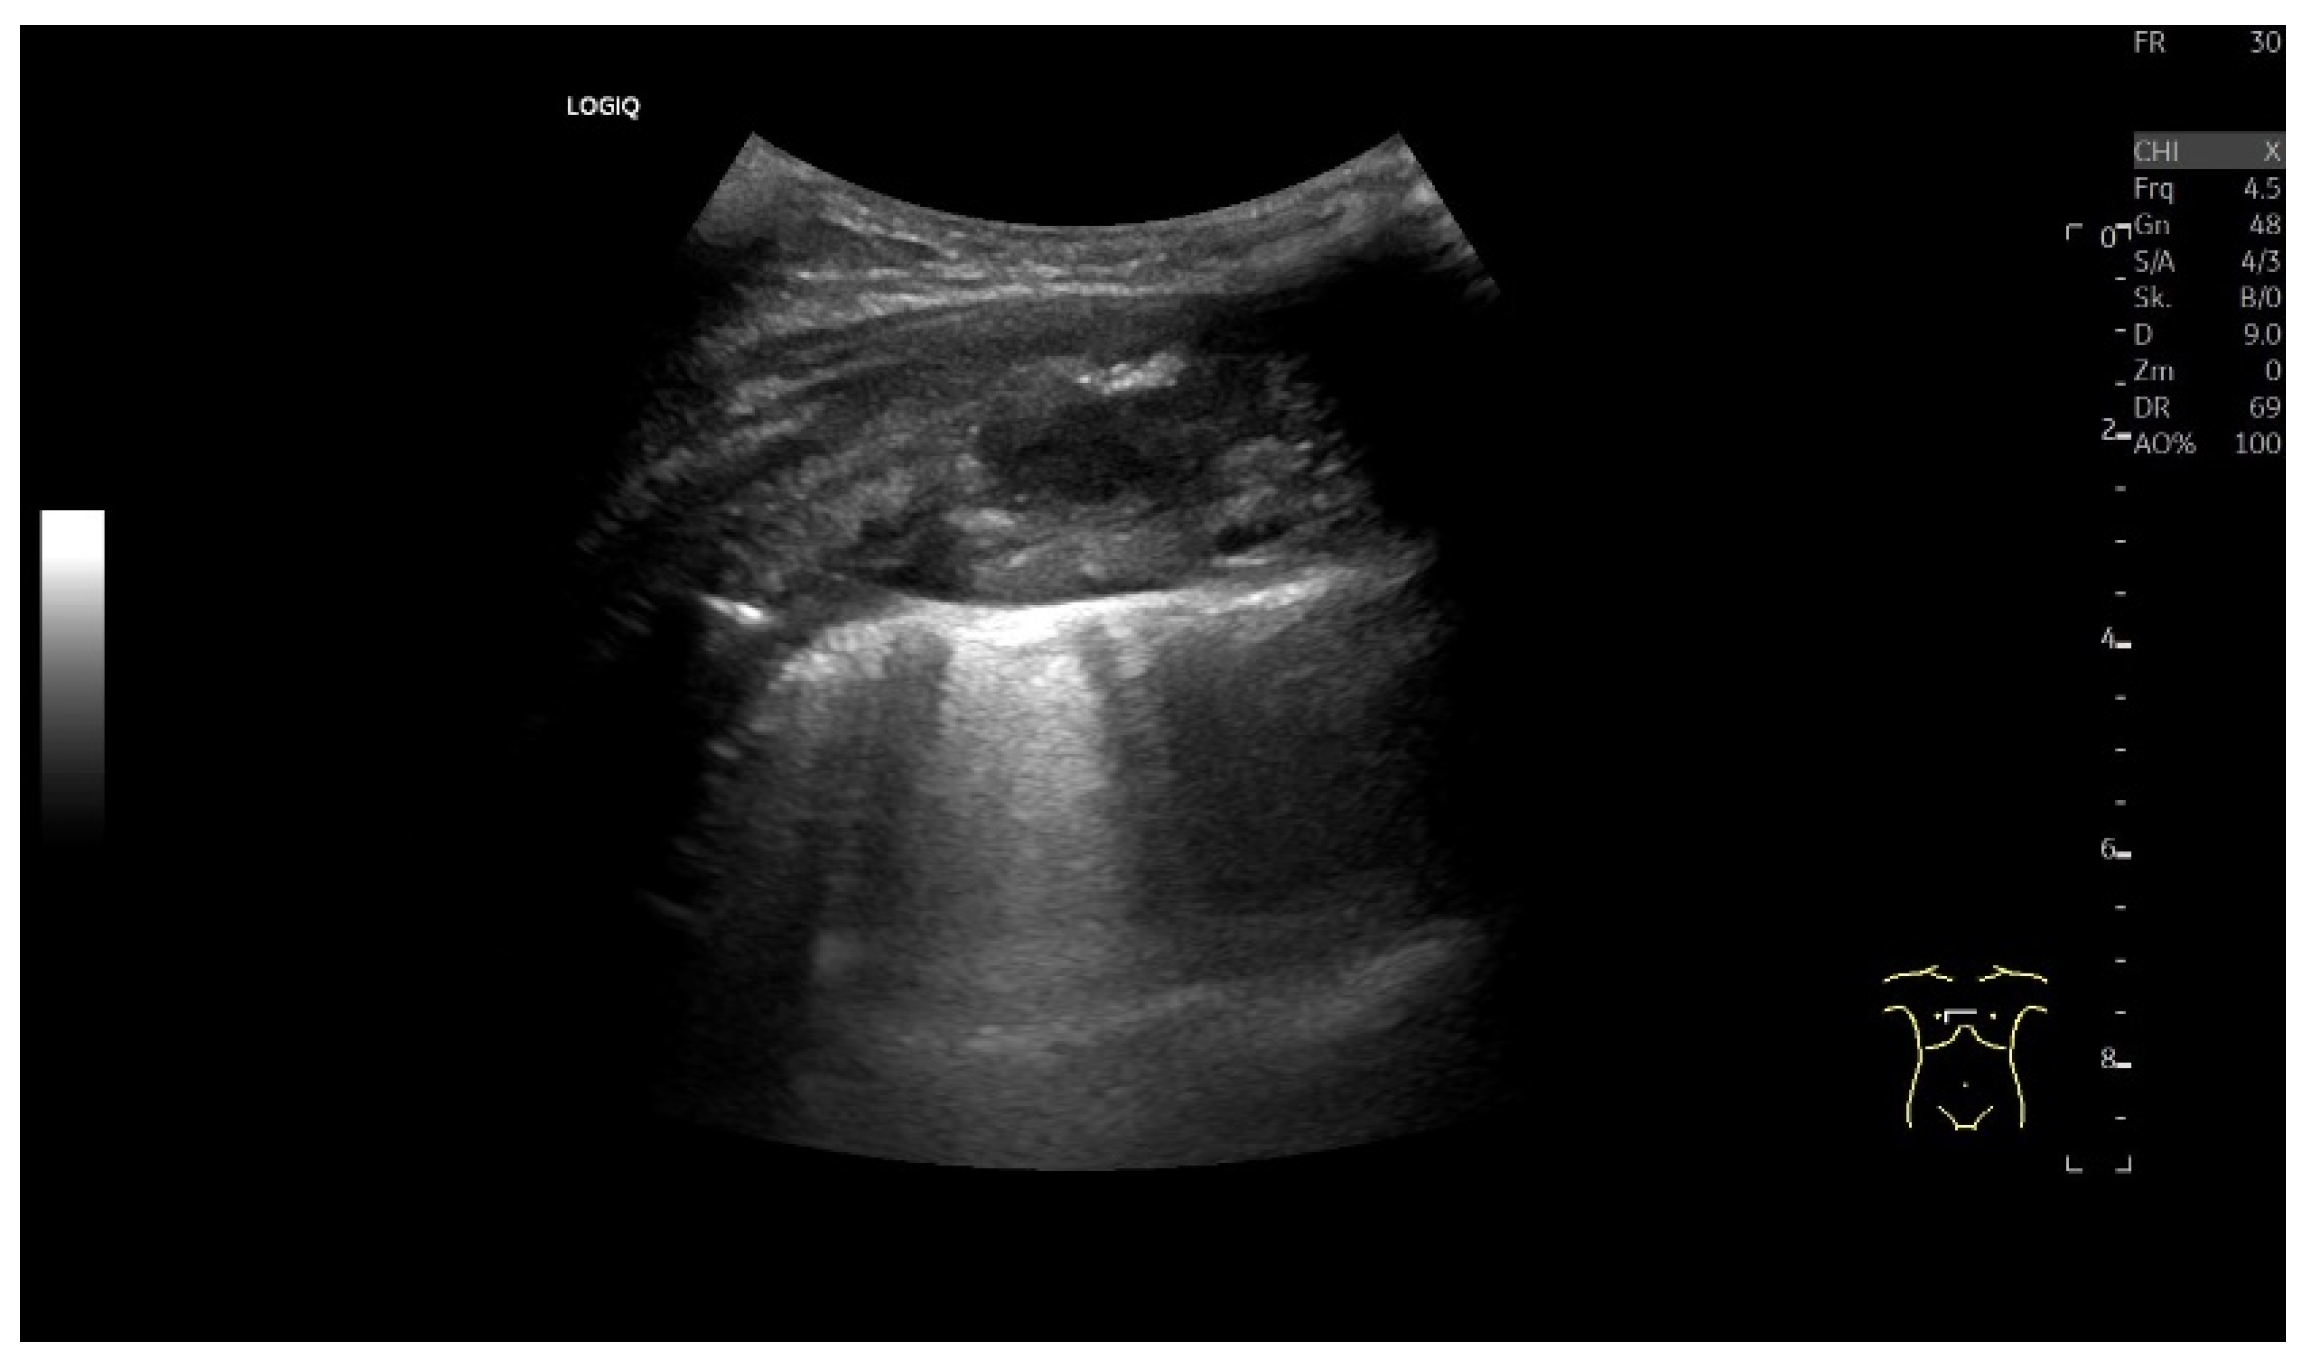

| Empyema | Hypoechoic thickened pleura, internal echos in the pleural effusion, hypoechoic pus, hyperechoic gas reflexes, fibrin strands, and chambering. In the phase of organization, thickened pleura, chambering of the pleural space. |

| Empyema necessitans | Exceeds the parietal pleura and infiltrates the surrounding soft tissue and chest wall muscles. |